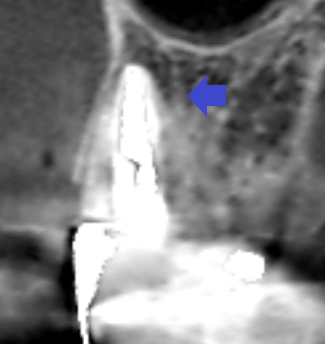

上顎第一大臼歯の冠状断のCT画像です。

矢印の先に矢状断のCT画像ではみられなかった膿の影が認められます。CT画像で歯を観る角度を変えることによって、近心頬側根にある膿が確認できました。根管充填は、根尖まで届いておらず、更に石灰化しています。難症例の根管治療です。